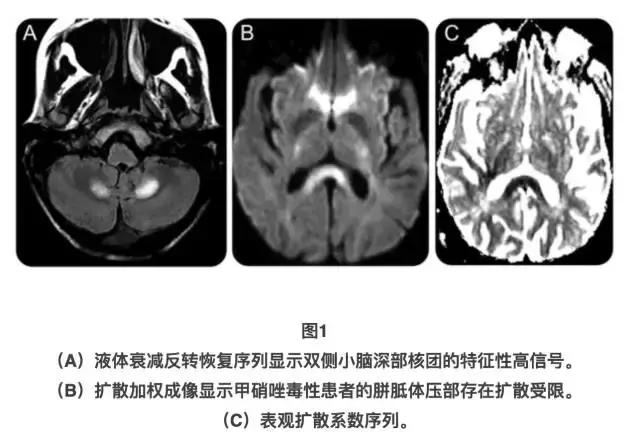

所有甲硝唑相关性脑病患者的脑部MRI均存在异常。甲硝唑相关神经毒性的典型MRI改变是小脑齿状核部位出现T2高信号,并伴有不同程度的脑干、胼胝体或其他部位受累(图1)。一例孤立的头孢托仑酯毒性报告显示,患者的双侧额叶皮质存在T2高信号。

在脑CT检查方面,除了1例甲硝唑毒性患者存在小脑低密度改变、1例伴有全身性痫性发作且脑电图(EEG)存在痫样放电的亚胺培南毒性患者,存在左侧丘脑低密度改变之外,其它患者的该项检查均未见异常。

3型:仅见于甲硝唑相关性脑病,其特点是在开始用药数周后发病,常有小脑功能障碍,痫性发作和EEG异常均罕见,且后者多无特异性,此外,还有广泛性脑部MRI异常。